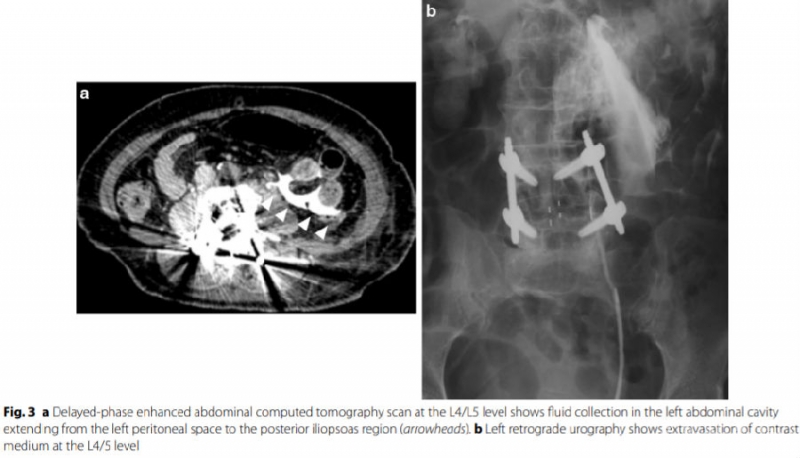

输尿管损伤有时在术中难以发现,病人在术后如出现腹部疼痛、发热、呕吐、长时间肠梗阻等症状,查体腹部有压痛、反跳痛、肌紧张,就应该考虑是否存在输尿管损伤;而腹部增强CT和逆行尿路造影能够及时的帮助我们诊断。

参考文献:Kubota G , Orita S , Umimura T , et al. Insidious intraoperative ureteral injury as a complication in oblique lumbar interbody fusion surgery: a case report[J]. Bmc Research Notes, 2017, 10(1):193.